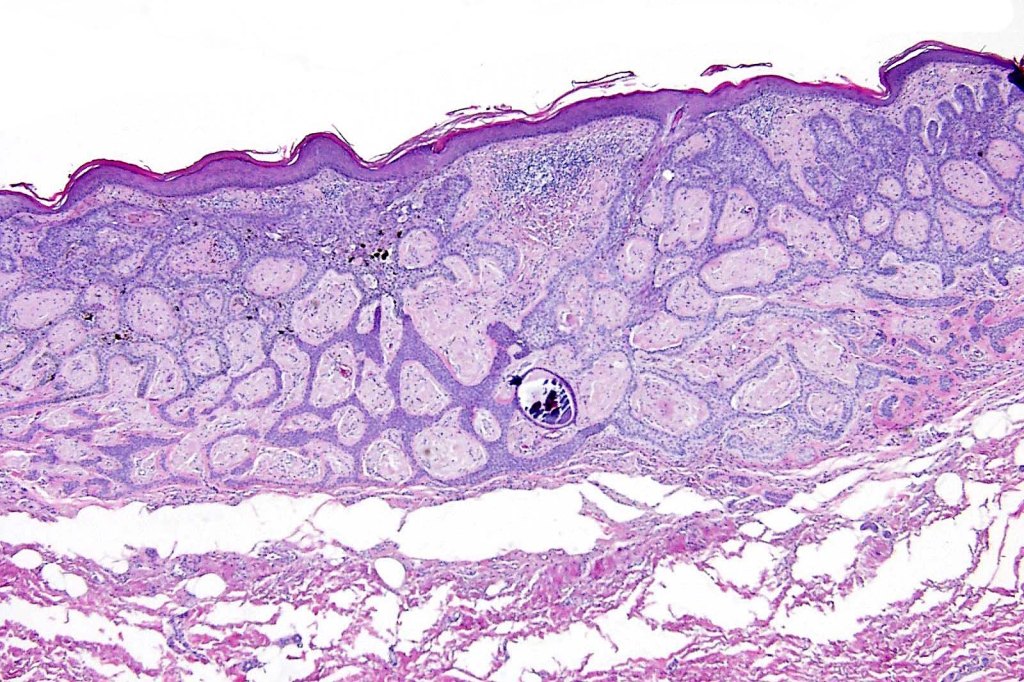

Histological features

•Multifocal origin from epidermis

•Anastomosing basaloid, narrow epithelial strands associated with a prominent fibrous (sometimes myxoid) stroma

•Peripheral palisade

•Round to oval vesicular nuclei with small nucleoli

•Mitoses very scanty or absent